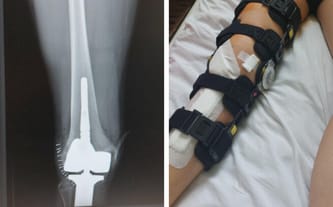

Kostniakomięsak kości piszczelowej prawej; podejrzenie przerzutów do płuc